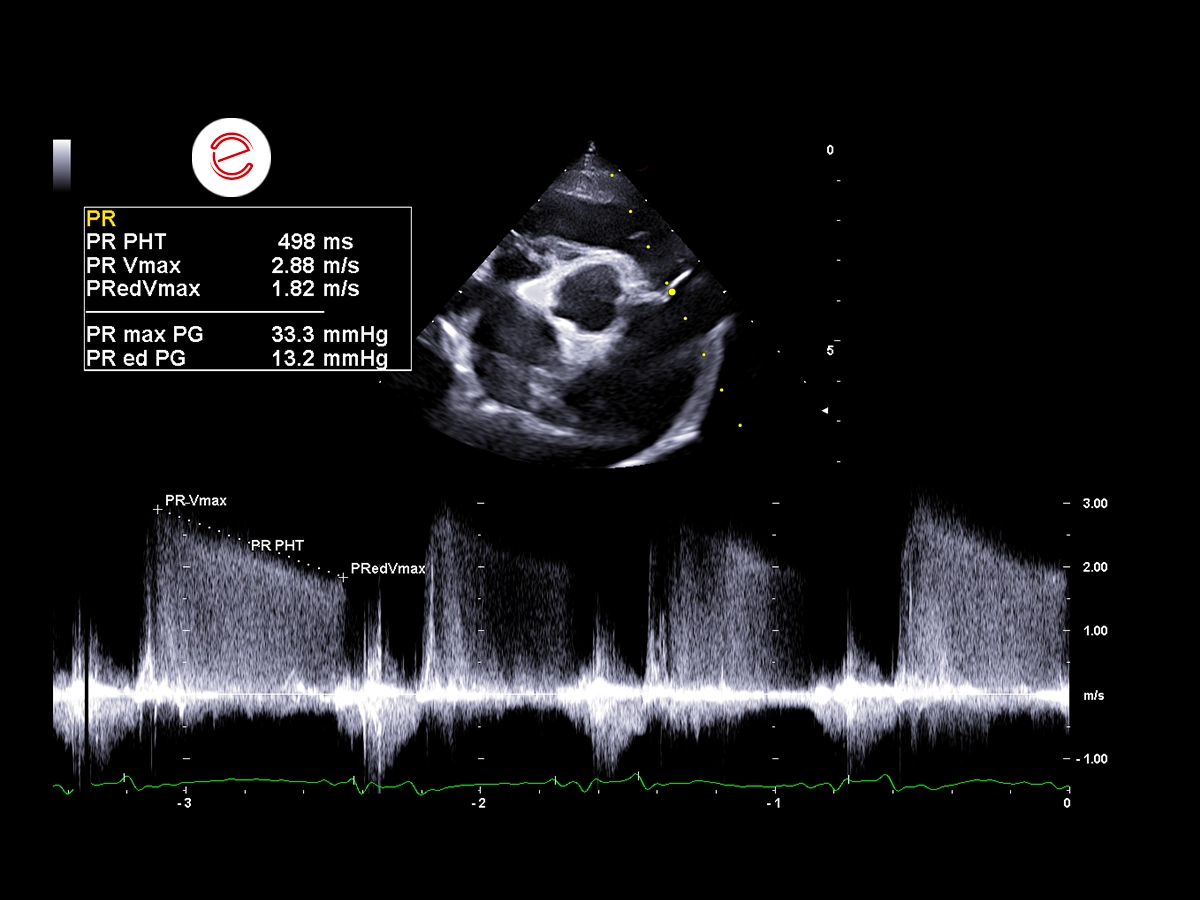

Pulmonary hypertension is suspected to be developing, as evidenced by a pulmonary regurgitation jet velocity of 2.88 m/s, generating a calculated pressure gradient of 33.3 mmHg, which falls within the range consistent with mild pulmonary hypertension.